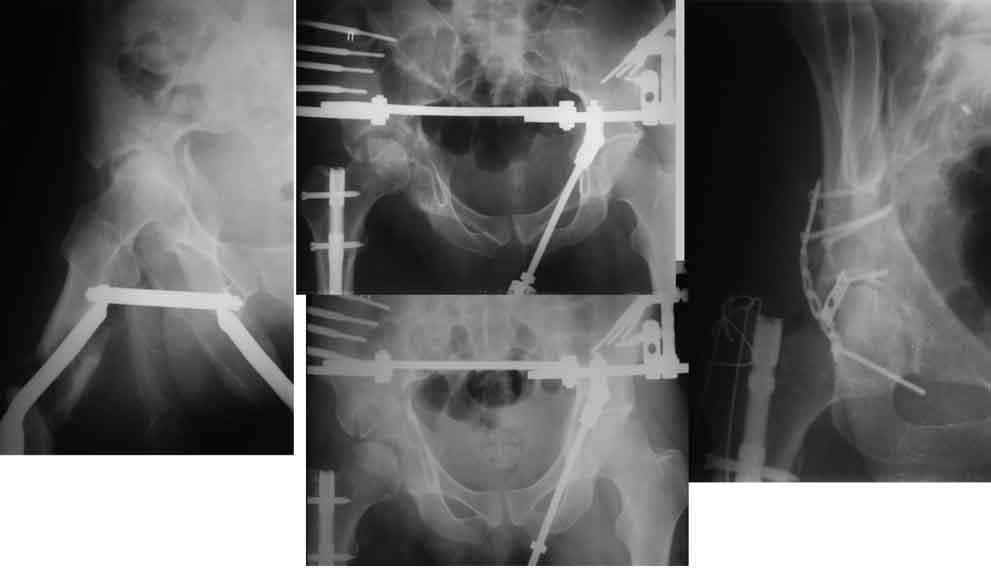

Пример с антеградным введением стержня (застарелый случай)

У тебя тоже можно воспользоваться этой методой, однако настоятельно рекомендую ЗИМО делать в аппарате (дистракционном устройстве) и лишь потом открыто вертлугу.